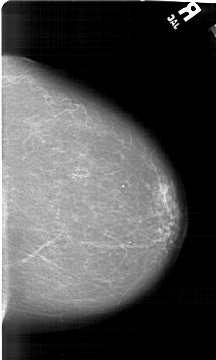

A_1492_1.LEFT_MLO

LEFT_MLO LINES 6181 PIXELS_PER_LINE 4246 BITS_PER_PIXEL 12 RESOLUTION 43.5 OVERLAY